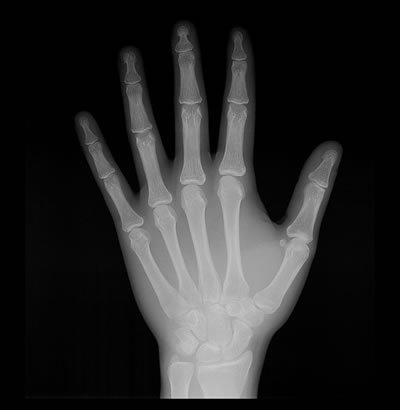

Carpal